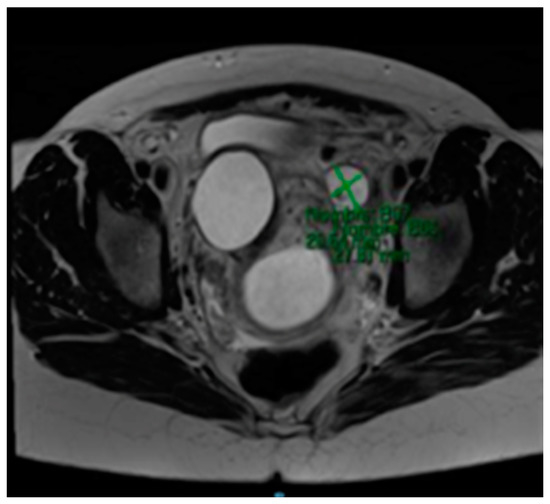

The MRI (Magnetic Resonance Imaging) scan showed 53 mm × 46 mm thin-walled cysts with a septum in the right paracervical area, another 27 mm × 20 mm cystic formation in the left hemipelvis (Figure 2 and Figure 3) and presacral 2 cm cysts containing a solid pole.

Figure 2. MRI scan compatible with 27 mm × 20 mm cystic formation in the left hemipelvis.